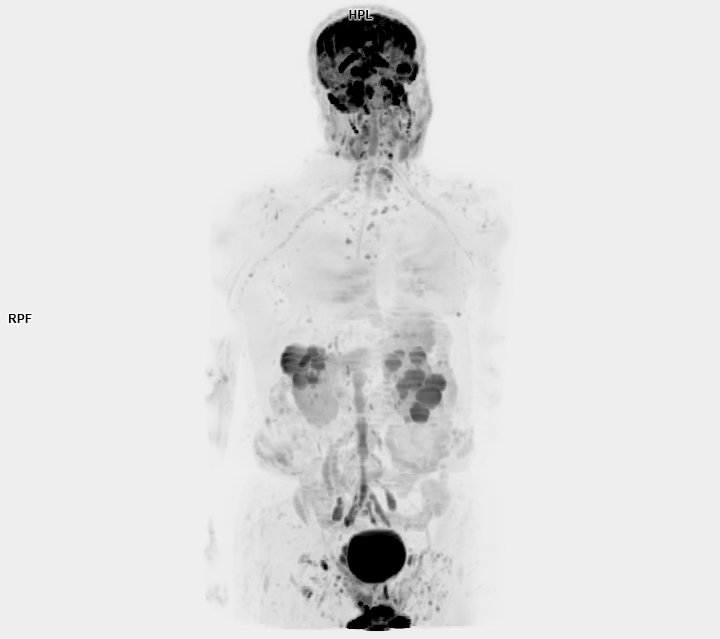

3 Tesla MR Çekim Görüntüleri

• 3 Tesla MR Çekim Görüntüleri